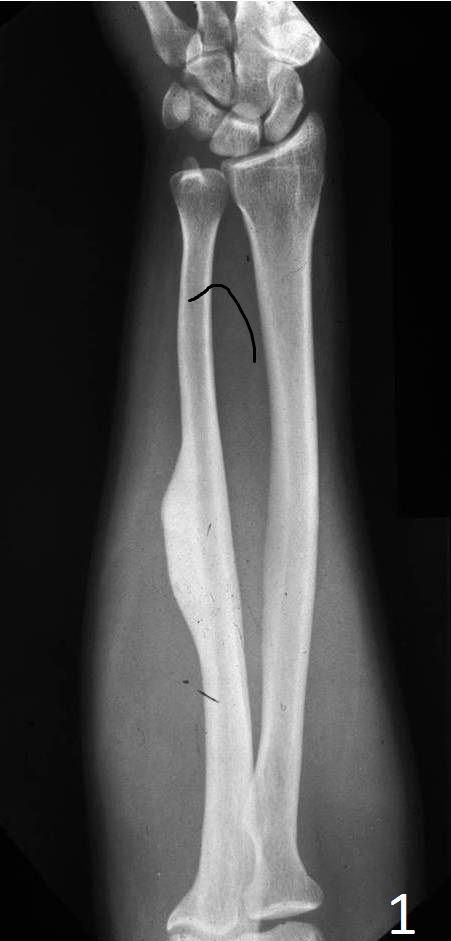

Plain x-ray

- Sharply defined, radiopaque smooth, homogeneous bone protruding from the surface of a bone

- Almost appears as a localized thickening of the bone